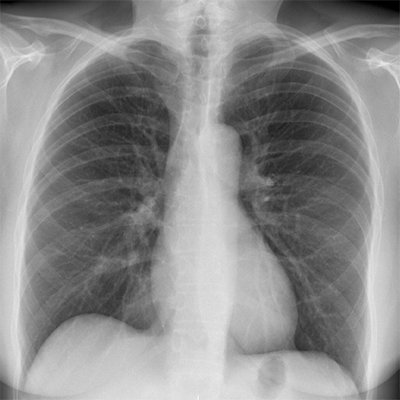

Présentation

La radiologie utilise les rayons X pour obtenir des images des structures internes du corps humain qui correspondent à une superposition. Les images obtenues sont appelées radiographies.

Nous réalisons tous les types de radiographie. La plupart ne nécessite aucune préparation spécifique.

Une échographie peut parfois être réalisée dans les suites pour approfondir le bilan et affiner le diagnostic.